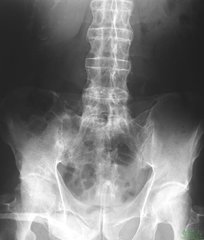

强直性脊柱炎的病因?身体上存在着很多的部位,但脊椎对于我们来说,非常的重要,如果脊椎出现什么问题,患者的身体行动就会非常的不便,很多的事情都无法去做,甚至需要家属的照看。而强直性脊柱炎就是这种非常严重的疾病。那么,强直性脊柱炎的病因是什么呢?

强直性脊柱炎的病因